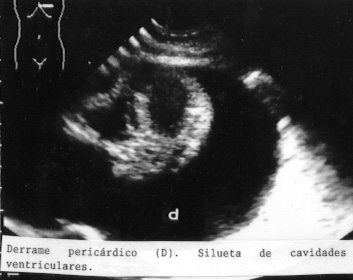

En la Fig 53 se observa un derrame con adherencias y una atelectasia.